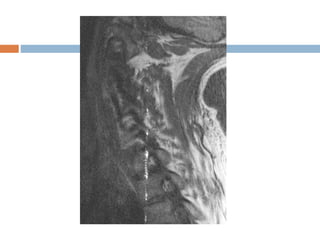

 Occurs at high contrast boundaries.

 Due to truncation(omission) of sampled signals.

 Commonly seen at the low signal intensity spinal

cord with high signal intensity CSF on T2WI of the

spine.

 As the signal is sampled, some data is necessarily

omitted in k-space, causing the signal intensity of

a given pixel to vary from its ideal signal intensity.

 Appearance

 Bright and dark lines.

 Solution

 Increase matrix size.

Gibbs or truncationartifact  Occurs at high contrast boundaries.  Due to truncation(omission) of sampled signals.  Commonly seen at the low signal intensity spinal cord with high signal intensity CSF on T2WI of the spine.  As the signal is sampled, some data is necessarily omitted in k-space, causing the signal intensity of a given pixel to vary from its ideal signal intensity.  Appearance  Bright and dark lines.  Solution  Increase matrix size.